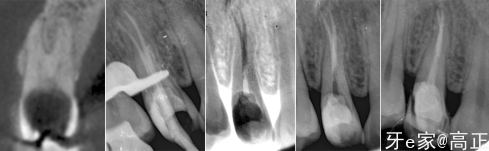

根管预备

放置氢氧化钙封药

侧面检查是否存在悬突

X片检查